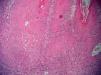

Piel. Formación continuada en dermatología Carcinoma epidermoide de pene

Carcinoma epidermoide de pene

Squamous cell carcinoma of the penis